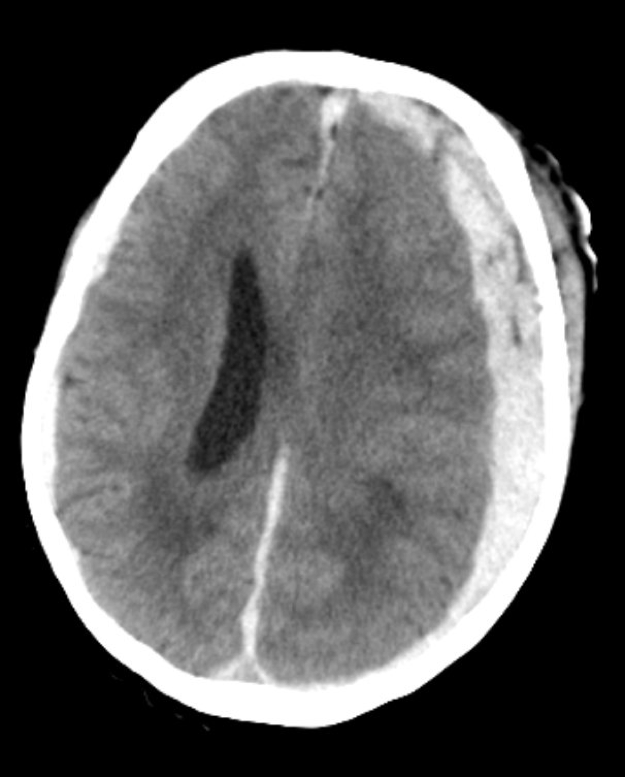

What is this? Where does the blood accumulate?

subdural hematoma

blood accumulates between the dura mater and the arachnoid mater

What vessel is torn in subdural hematoma?

bridging veins